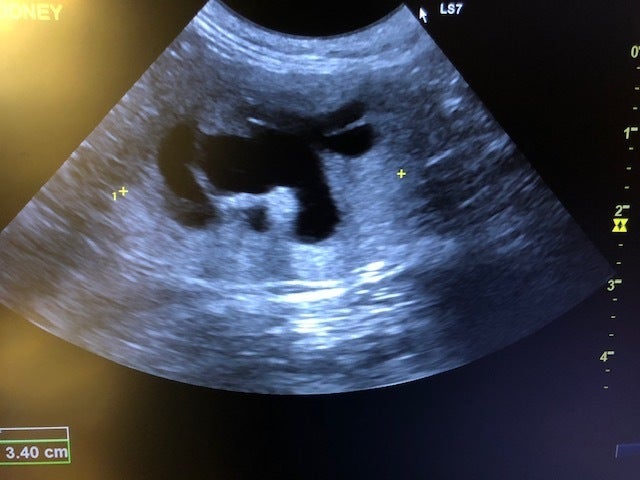

猫は腎臓病になり易いといわれますが、特に高齢の猫はその傾向にあります。

キジ白の「ちび」は、まだ1歳半(推定)。

近隣の公園に数か月前に現れ、先住の地域猫と喧嘩しながらでも楽しそうに暮らしていました。

とても人懐っこいちびは、公園を散歩しているご夫婦のところへ、引き取られることになりました。

安全な室内で生活し始めた矢先、ご飯を食べなくなり、病院へ。

末期の腎不全。

腎臓は形をなさず、余命宣告を受けたご夫婦は、最期までお世話して看取る事を覚悟されましたが、

愛犬を看取ったばかりで、看取りの辛さに耐えることができず、受入のご相談。

2021年1月20日 ととの森で受け入れることになりました。